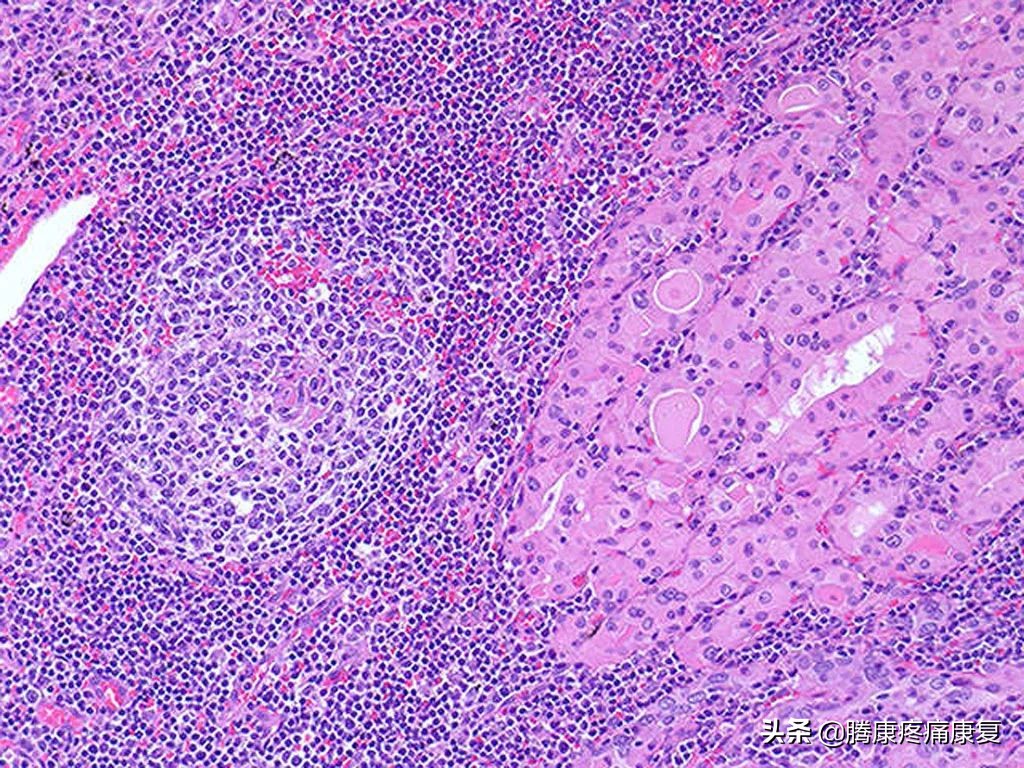

甲状腺细针穿刺病理检查可见,中或大量淋巴细胞浸润,形成滤泡和发生中心。同时还可以使用甲状腺超声检查和甲状腺核素显像辅助检查。